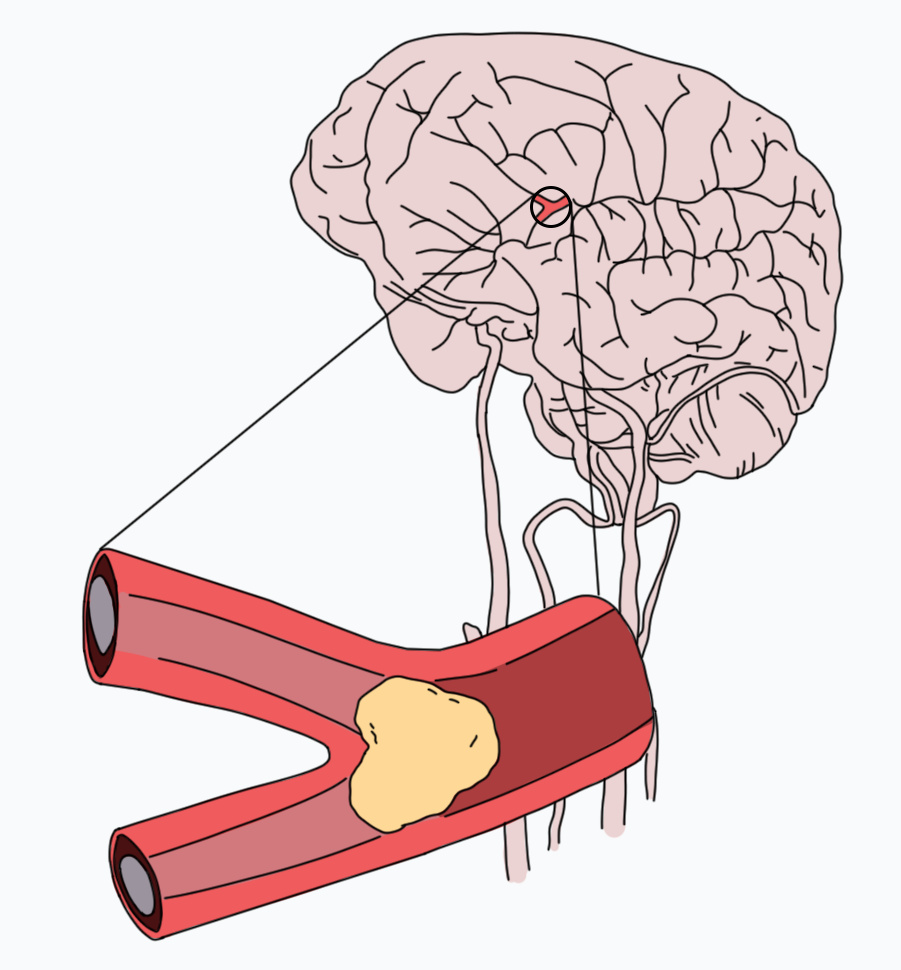

В широком смысле инсульт — это повреждение тканей мозга в результате нарушения кровообращения. По механизму воздействия его принято делить на два типа: ишемический, при котором клетки мозга недополучают крови и отмирают, и геморрагический, когда крови, наоборот, слишком много, она выходит из кровеносных сосудов и заливает часть мозга. В зависимости от места кровоизлияния геморрагический инсульт делят на внутримозговой и субарахноидальный; при последнем кровь попадает в пространство между оболочками мозга, в норме заполненное спинномозговой жидкостью.